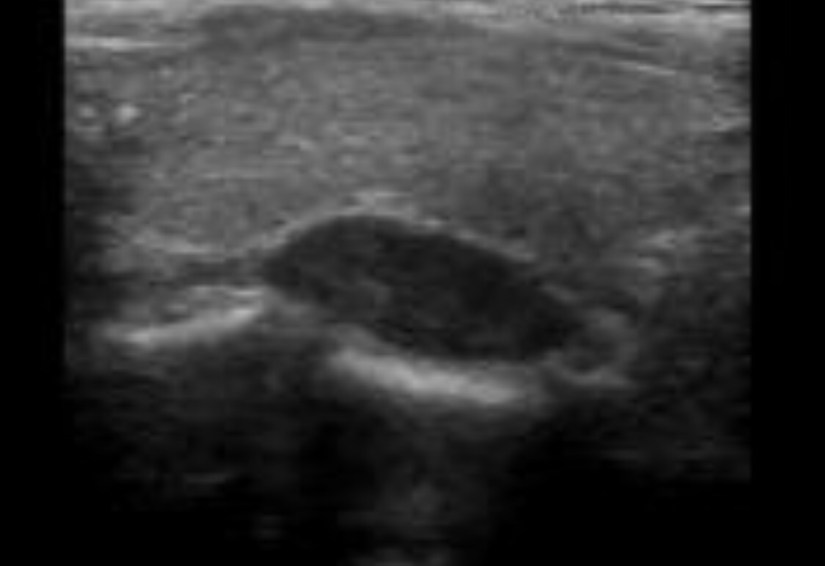

👉Neck ultrasound is complementary to sestamibi scan for parathyroid localization and can also identify thyroid nodules that need concurrent management